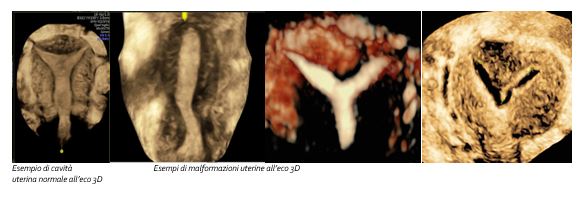

Ecografia ginecologica tridimensionale

Che cos’è

L’ecografia tridimensionale consente di studiare contemporaneamente un determinato settore dell’organo interessato sui tre piani ortogonali e di ricostruirne un volume. È indicata in tutti in casi in cui una semplice ecografia di primo livello non sia in grado di fornire un adeguato inquadramento diagnostico di una paziente o nel caso in cui sia necessario raccogliere dati aggiuntivi, non ricavabili da una tecnica di base.

Un ulteriore vantaggio dell’ecografia tridimensionale è la possibilità di archiviare i volumi e di studiarli successivamente, procedimento particolarmente utile nell’inquadramento di patologie complesse o rare o per una migliore gestione della paziente pre e post-trattamento. Manipolando le immagini che otteniamo possiamo valutare con grande rapidità in ogni paziente la forma e le caratteristiche della cavità uterina per escludere difetti che possano ostacolare l’insorgenza o il buon decorso della gravidanza in pazienti infertili o poliabortive e diagnosticare con grande precisione.

L’esistenza di patologie della cavità uterina come le malformazioni uterine, i polipi endometriali o i fibromi sottomucosi e le irregolarità o ispessimenti della zona giunzionale come nell’adenomiosi, che possono causare problemi di tipo emorragico nelle pazienti di ogni età, particolarmente nel periodo tra i 40 anni e la menopausa.

L'aggiunta della tecnologia tridimensionale (3D) è relativamente nuova ed alcuni studi hanno dimostrato che questo approccio potrebbe garantire prestazioni migliori rispetto alle immagini bidimensionali classiche, con il vantaggio inoltre di esplorare ed elaborare le immagini non in presenza della paziente, consentendo a più lettori di studiare i dati ecografici